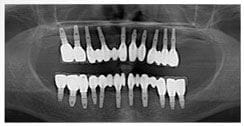

X 光片

術前X光片

術後X光片